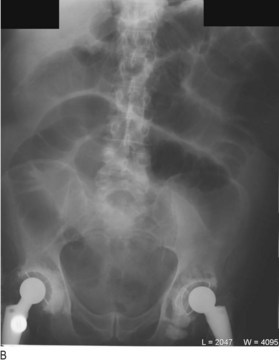

Fig. 8.29 Radiography in gastrointestinal disease.

(A) Air under the diaphragm on chest X-ray due to perforated duodenal ulcer. (B) Dilated small bowel due to acute intestinal obstruction. (C) Dilated large bowel due to toxic megacolon. (D) Dilated loop of large bowel due to sigmoid volvulus.